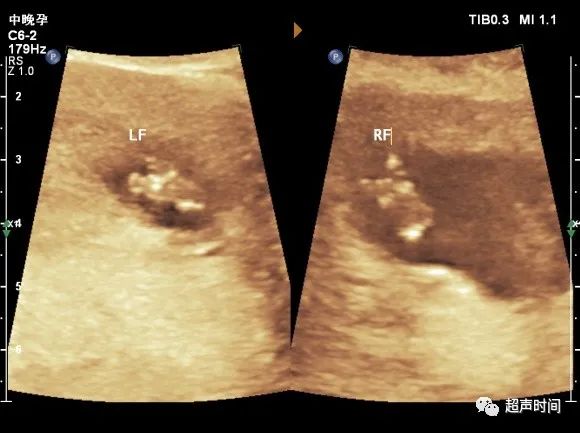

图 3 孕 13ᐩ 周。足底切面显示胎儿双足呈「V」形自足底中央部裂开,V 形尖端指向脚掌

图 4 孕 17ᐩ 周。足底切面更清楚显示胎儿双足「V」形裂开征象